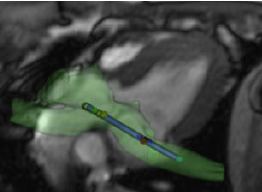

This project is likely a series of meetings with key OpenIGT parties to discuss CARMA progress in RT MRI and our software plans. We have some prototype code in Slicer for catheter tracking using special coils on the catheter and special MRI tracking sequence. We would like to discuss our project with other interested RT MRI and OpenIGT parties.